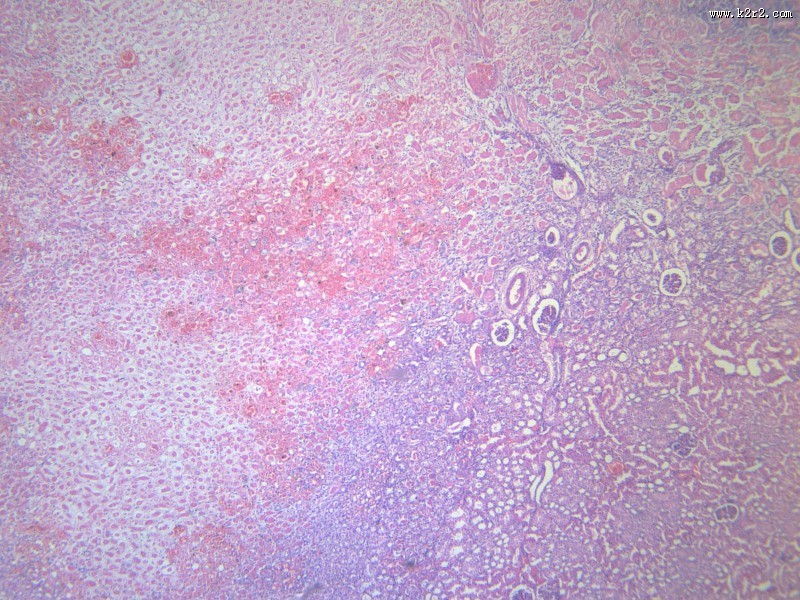

肾凝固性坏死 - 第4张

肾凝固性坏死

肾小管坏死

kidney coagulative necrosis